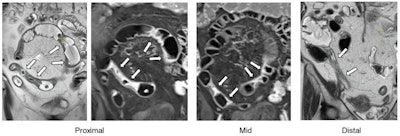

Coronal single-shot fast spin-echo and postgadolinium images demonstrate the proximal, mid, and distal aspects of a naive stricture at MR enterography performed in a 71-year-old female patient. There is a long inflammatory stricture with multifocal areas of luminal narrowing and intervening areas of active inflammation involving the terminal ileum. The four central readers measured this stricture as being 70.1 cm, 69.8 cm, 71.7 cm, and 71.6 cm in length … The arrows point to a single stricture that was assessed by all readers. Colored dots in the left-most and right-most images are reader markings along the lumen of the stricture. Postgadolinium images are the middle images. Images and caption courtesy of the RSNA.